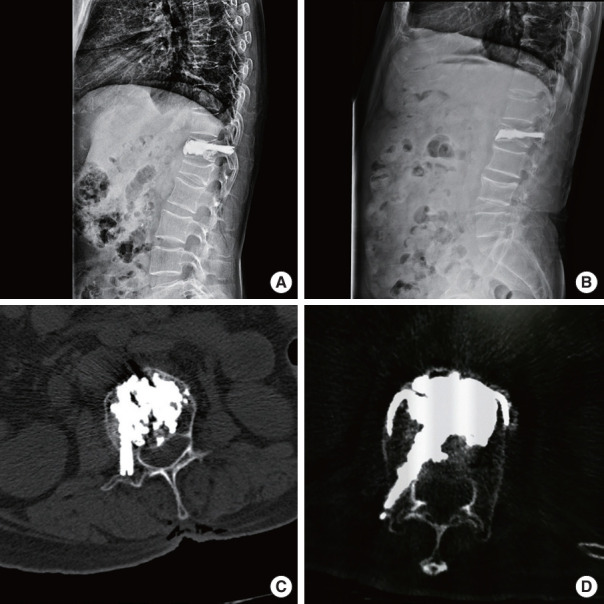

Methods: From May 2017 to May 2021, 77 patients with single-level unstable KD were included in the PPP group, and 42 patients received the PVP-bone cement bridging screw system were included in the screw group. The changes in the vertebral body index (VBI), bisegmental Cobb angle, visual analogue scale (VAS) and Oswestry Disability Index (ODI) and the cement loosening rate and displacement rate at different follow-up time points were used to evaluate the clinical efficacy.

Results: There was no significant difference in VBI or bisegmental Cobb angle between the 2 groups (p > 0.05) before operation, immediately after operation and at 6-month followup, while at 1-year and 2-year postoperative evaluations, the screw group had higher VBI and bisegmental Cobb angle than the PPP group (p < 0.05). Before operation, immediately after operation, at 6-month and 1-year follow-up, there was no significant difference in VAS or ODI score between the 2 groups (p > 0.05), while at 2-year follow-up, the screw group still had higher VAS and ODI scores than the PPP group (p < 0.05). No bone cement displacement occurred in both groups, but the rate of bone cement loosening was 14.29% in group PPP, and 0 in screw group (p < 0.05).

Conclusion: This 2-year follow-up study shows that the PVP-bone cement bridging screw system combined therapy had better midterm treatment efficacy than the PVP-PPP combined therapy in patients with unstable KD, and the bone cement bridging screw system is a preferred therapy with better anti cement loosening ability.